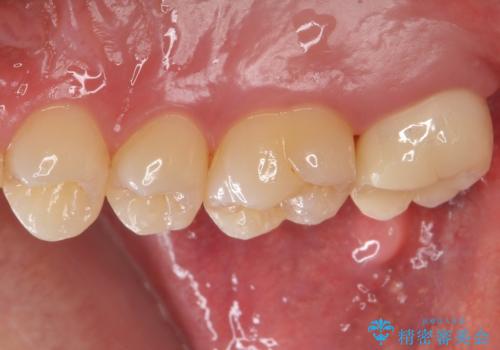

ブラッシングが上手な患者様であったため歯茎の締りもよく、大変適合の良い被せ物を装着することができました。

銀歯をなくしたい ジルコニアクラウンでの修復